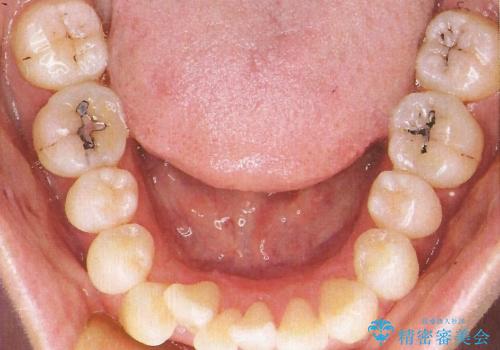

- リンガルブラケット

裏側からの矯正であったため、表側に比べて少し治療期間を要しました。

目立たずに矯正治療を終えることができ、満足していただけました。